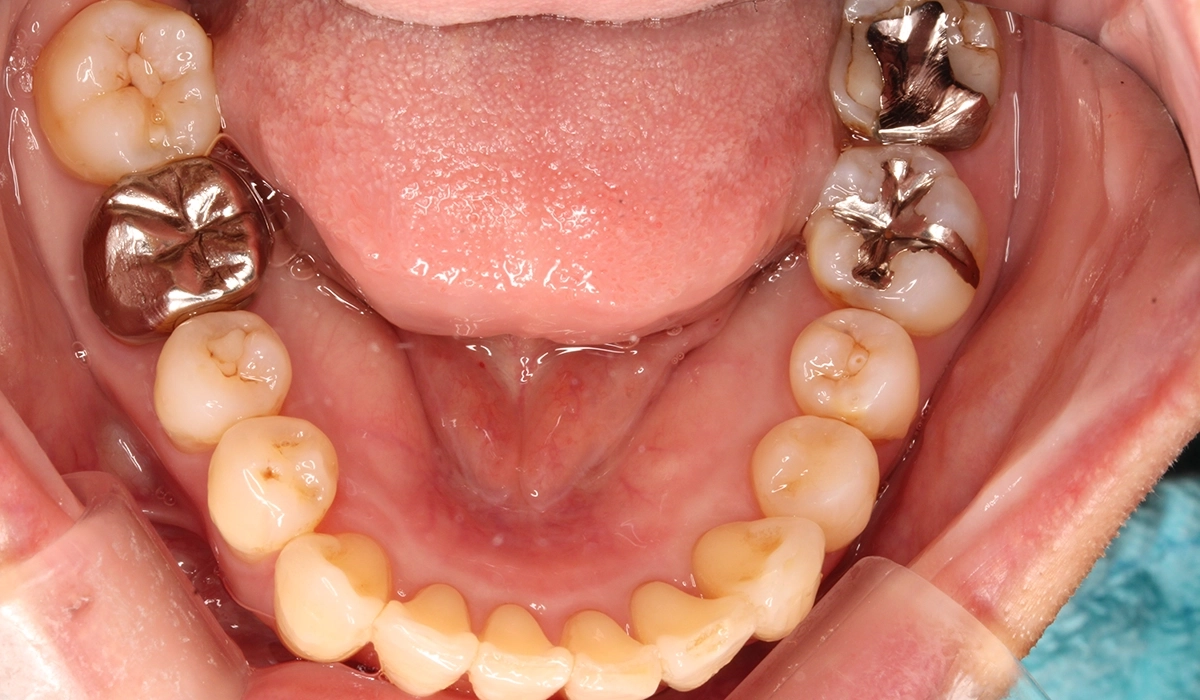

術後:上顎

術後:下顎